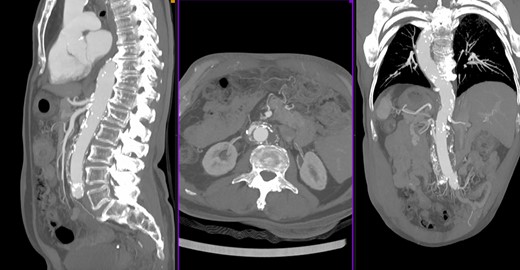

We report a case of a 73-year-old man with known SIT and past medical history of hypertension and dyslipidemia, no other comorbidities (ASA referred to our center for a specific abdominal pain); an US exam was performed, and an abdominal aortic aneurysm (AAA) was found. A followed computed tomography scan showed a 6 × 7 cm pararenal aortic aneurysm (pAAA). The pAAA was extended caudally to the aortic bifurcation with no evidence of rupture (Fig. 1). The diameter of the aorta at lower left renal artery was of 36 mm. The origins of the others visceral vessels were very close and in a short aortic segment. As we usually make for complex aortic cases, a careful multidisciplinary evaluation of comorbidities was performed. Therefore we have proposed an open repair with supraceliac clamping and visceral protection with left–left (anatomically right) heart bypass (LHB). Operation room setup, patient–surgeon position and pump placement were mirrored as compared to routine thoraco–phreno–laparotomy access (Fig. 2). Under general anesthesia, both surgical right axillar and femoral arteries were prepared. We used the axillar artery for the LHB in-line. The femoral artery was prepared for the line-out of the shunt in eventual need of total thoracoabdominal replacement with a long-time perfusion. By a right retroperitoneal approach, we prepared the aorta up to below the diaphragm. Pillars of the diaphragm were sectioned to prepare the better site to clamp the aorta. After systemic heparinization, the aorta was clamped above the celiac trunk. The aorta was opened; both renal arteries, superior mesenteric artery and celiac trunk were cannulated with 9-Fr Pruitt catheters connected to the pump. Therefore, the visceral vessels and the renal arteries were perfused with isothermic blood from the LHB circuit (Medtronic Biomedicus 560 centrifugal pump). Both common iliac arteries were endo-clamped with Fogarty catheters. The left renal artery was disconnected, and an oblique end-to-end anastomosis between the proximal aorta (including the visceral vessels and the right renal artery takeoffs) and a straight 18-mm Dacron graft was performed. The distal anastomosis was constructed at the level of the aortic bifurcation, and subsequently the left renal artery was replaced on the tube graft with T-L anastomosis (Fig 3). Postoperative course was uneventful, and the patient was discharged on 6th postoperative day. Follow-up CT scan 6 months after the intervention showed a good treatment of the aneurysm with a patency of all visceral vessels (Fig. 4).